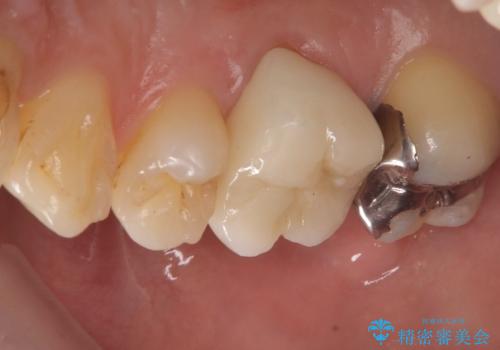

- 主訴:銀歯の入っている歯の側面に穴が空いている気がする。そこに食べ物が詰まる。

右上6番目の歯の被せものと歯質の境目に大きな窪みが出来ており、そこに汚れが停滞しやすい状態で虫歯もそこから広がっていたため、被せもののやり替えと必要に応じて土台の立て直しも行うこととしました。

メタルクラウンを除去したところ近心面に大きな窪みとう蝕を認め、ファイバ-コアからのやり替えとしました。クラウンは審美性の良いセラミッククラウンを選択されました。